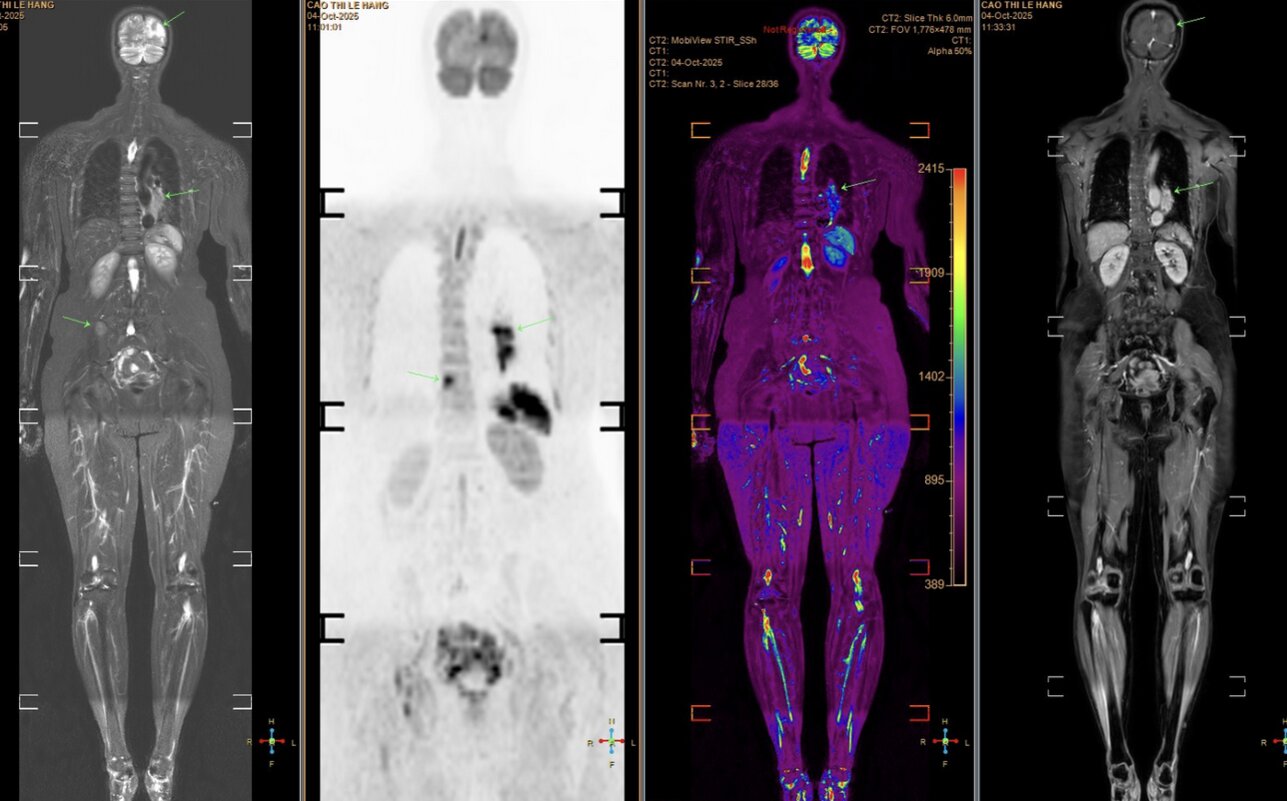

Tuy nhiên, các triệu chứng ngày càng nhiều và nặng hơn, bệnh nhân mới chịu đi khám sức khỏe. Kết quả chụp MRI cho thấy nhiều ổ tổn thương di căn dạng biểu mô tuyến. Khi chụp CT ngực, bác sĩ phát hiện một khối u lớn ở đáy phổi trái, xác định là ung thư phổi giai đoạn muộn, đã di căn sang nhiều cơ quan, trong đó có não bộ. Tiên lượng bệnh rất xấu.